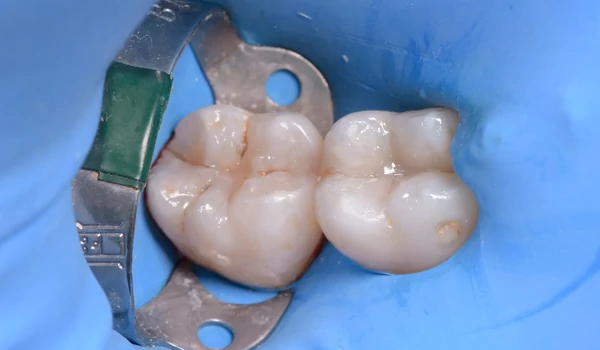

6. ábra A feltöltés befejeződött. |

7. ábra Szép felületi morfológia és árnyalatbeli beolvadás. |